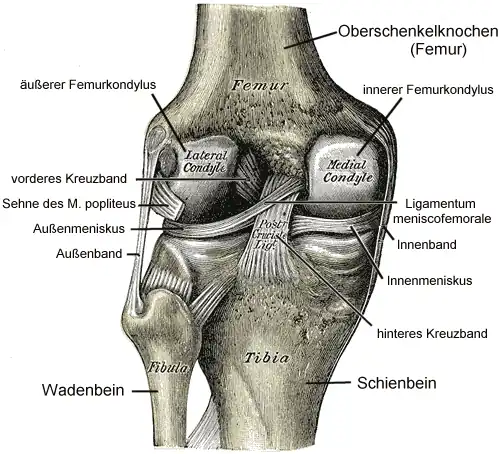

Oberschenkelknochen

Der Oberschenkelknochen endet kniewärts (distal) mit zwei recht breiten, leicht nach außen gekrümmten (konvexen) Gelenkknorren (Condylus lateralis femoris und Condylus medialis femoris), die von vorne nach hinten verlaufen und zwischen denen auf der Rückseite eine schmale Grube (Fossa intercondylaris) liegt. Die Oberfläche der Gelenkknorren (Condyli ossis femoris) ist spiralförmig angelegt, so dass der Mittelpunkt der Drehbewegung des Gelenkes unter der Bewegung eine spiralförmige Bewegungsbahn beschreibt. Der innere Gelenkknorren ist in waagerechter Richtung (sagittal) ein bis zwei Zentimeter größer als der äußere und steht weiter vom Gelenk entfernt.

Die Oberschenkelknorren divergieren etwas gelenkferner und nach hinten. Der äußere Gelenkknorren ist vorne breiter als hinten, während der innere Gelenkknorren eine gleichmäßige Breite besitzt. In horizontalen Ebenen sind die Gelenkknorren um eine vertikale Achse nur leicht gekrümmt. In der vertikalen Ebene nimmt die Krümmung nach hinten zu, das heißt, der Krümmungsradius wird kleiner. Der innere Gelenkknorren ist noch zusätzlich um eine vertikale Achse gekrümmt (Rotationskrümmung).[2]

Schienbein

Das obere Ende des Schienbeines läuft ebenfalls in zwei, leicht nach innen gekrümmte Gelenkknorren (Condylus lateralis tibiae und Condylus medialis tibiae) aus. Dazwischen befinden sich ein erhabener Knochenfirst (Eminentia intercondylaris), der sich in zwei kleine Höcker unterteilt (Tuberculum intercondylare mediale und Tuberculum intercondylare laterale) und zwei Einmuldungen (Area intercondylaris anterior – bei Tieren Area intercondylaris cranialis – und Area intercondylaris posterior – bei Tieren Area intercondylaris caudalis). Die gesamte obere Fläche des Schienbeins wird als Schienbeinplateau bezeichnet, die die Gelenkfläche des Schienbeins (Facies articularis superior tibiae) für das Kniegelenk bildet. Da sich der Knochenfirst über das gesamte Schienbeinplateau erstreckt, bleibt die Drehbewegung als mögliche Bewegungsrichtung des Gelenkes erhalten.

Menisken

Man unterscheidet einen Innenmeniskus (Meniscus medialis), der C-förmig, größer und etwas unbeweglicher (da mit dem Innenband verwachsen) ist, und einen Außenmeniskus (Meniscus lateralis), der kreisförmig, kleiner und beweglicher ist (da er mit keinem Seitenband verwachsen ist). Die Menisken sind im Querschnitt keilförmig. Die hohe Kante liegt außen, die niedrige innen. Da die Oberschenkelknochen genau in der Mitte direkt auf dem Schienbeinplateau und peripher auf den Menisken aufliegen, tragen diese einen wesentlichen Teil der Last.

Die Menisken können vorne durch ein kurzes, kräftiges Band (Ligamentum transversum genus) verbunden sein, das aber variabel ist und keine Verbindung zum Schienbeinplateau hat. Als eigentliche Verankerung der Menisken strahlen die Fasern der Vorder- und Hinterhörner in das Schienbeinplateau ein und begründen damit die beträchtliche Zugfestigkeit. Zusätzlich können variabel angelegte Bänder (Ligamenta meniscofemoralia) den lateralen Meniskus mit dem inneren Oberschenkelknorren verbinden.[10]

Seitliche Bandsicherung

Das Knie hat zwei Seitenbänder: ein inneres (Ligamentum collaterale tibiale) und ein äußeres (Ligamentum collaterale fibulare). In Streckstellung sind beide Seitenbänder (auch Kollateralbänder genannt) gespannt und verhindern somit die Drehbewegung, in Beugestellung verkleinert sich der Krümmungsradius, Ursprung und Ansatz nähern sich einander an und die Bänder sind infolgedessen entspannt. Beide Seitenbänder stabilisieren das Kniegelenk in seitlicher Richtung (Frontalebene), damit ein Wegknicken in eine O-Bein-Stellung (Genu varum) oder X-Bein-Stellung (Genu valgum) verhindert wird.

Das Innenband (Ligamentum collaterale tibiale bzw. mediale) ist ein dreieckiges, flaches Band, das breitflächig vom Aufsatz des inneren Oberschenkelknochens (Epicondylus medialis femoris) zur Innenseite des Schienbeines (Facies medialis tibiae) verläuft. Es ist in die äußere Schicht der Gelenkkapsel eingebaut und mit dem Innenmeniskus verwachsen.

Das Außenband (Ligamentum collaterale fibulare bzw. laterale) ist ein kräftiges Band, das in seinem dorsalen Abschnitt zylinderförmig vom Aufsatz des seitlichen Oberschenkelknochens (Epicondylus lateralis femoris) zum Wadenbeinkopf (Caput fibulae) zieht. Es hat keine feste Verbindung zur Gelenkkapsel und den Menisken.

Hintere Bandsicherung

Zentrale Bandsicherung

Die Kreuzbänder (Ligamenta cruciata) ziehen von der Grube zwischen den Oberschenkelknorren zum Schienbein. Von der Seite und von vorn betrachtet überkreuzen sie sich dabei in ihrem Verlauf.

Vorderes Kreuzband

Hinteres Kreuzband